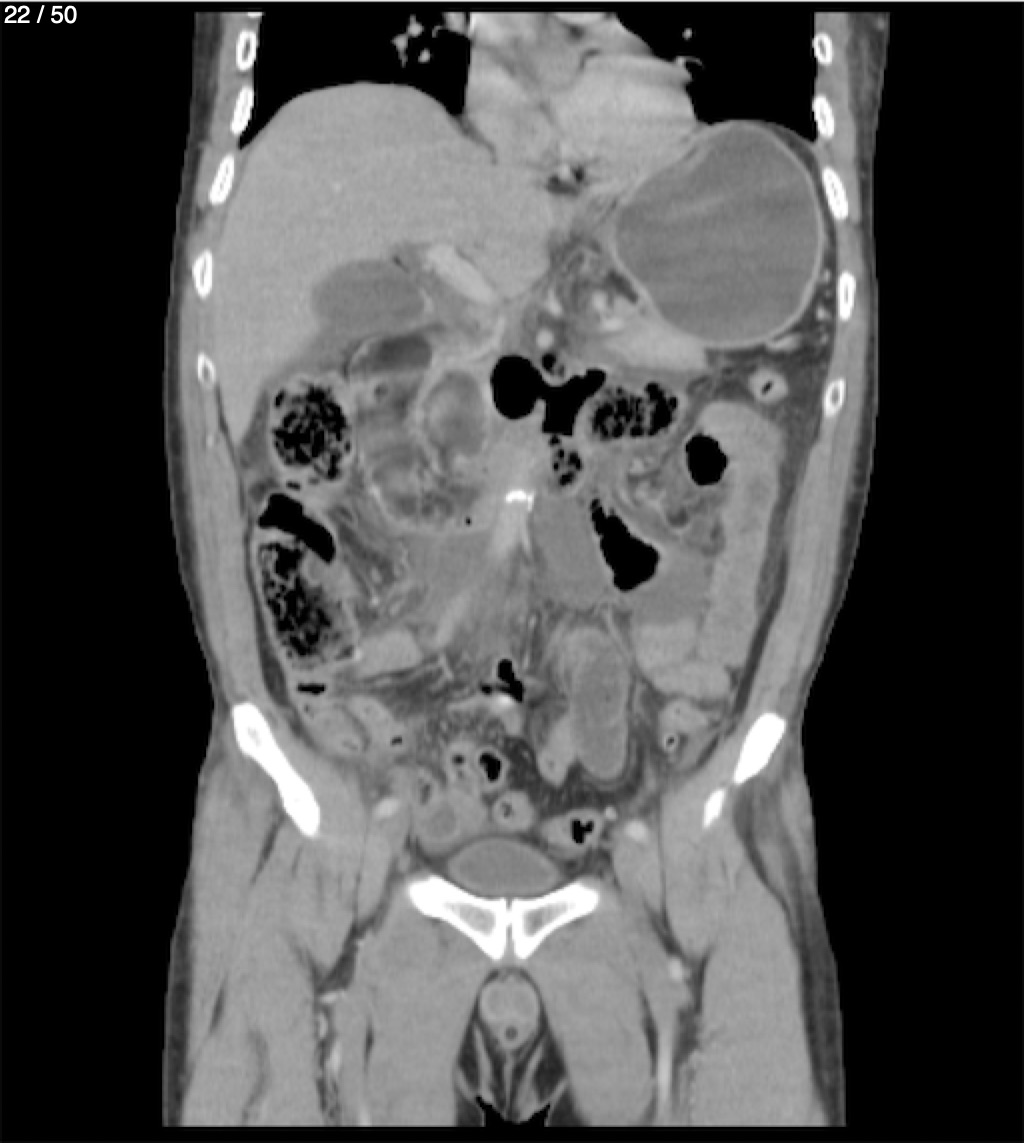

Alonso Victorio Ruiz 62A - T.C Abdomen Syc